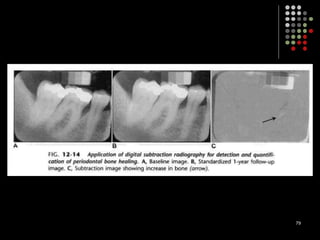

Digital subtraction radiography

77

Digital subtraction radiography Subtraction in digital radiology is another image enhancement method with purpose to produce two radiographs of the same area in the mouth at the different time intervals.  The first image can be subtracted from the second one to identify changes that may have occurred during a certain time period. Minimal changes in loss or gain of hard tissue can be detected using this technique, otherwise undetectable by visual examination and traditional radiography. 77